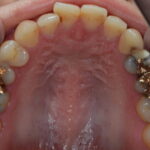

今回は金属でのブリッチをセラミッククラウンに変更した症例をご紹介します。

金属でブリッジ治療を行っている部分に違和感があるとご来院されました。

- ジルコニアクラウン 88,000円x3本